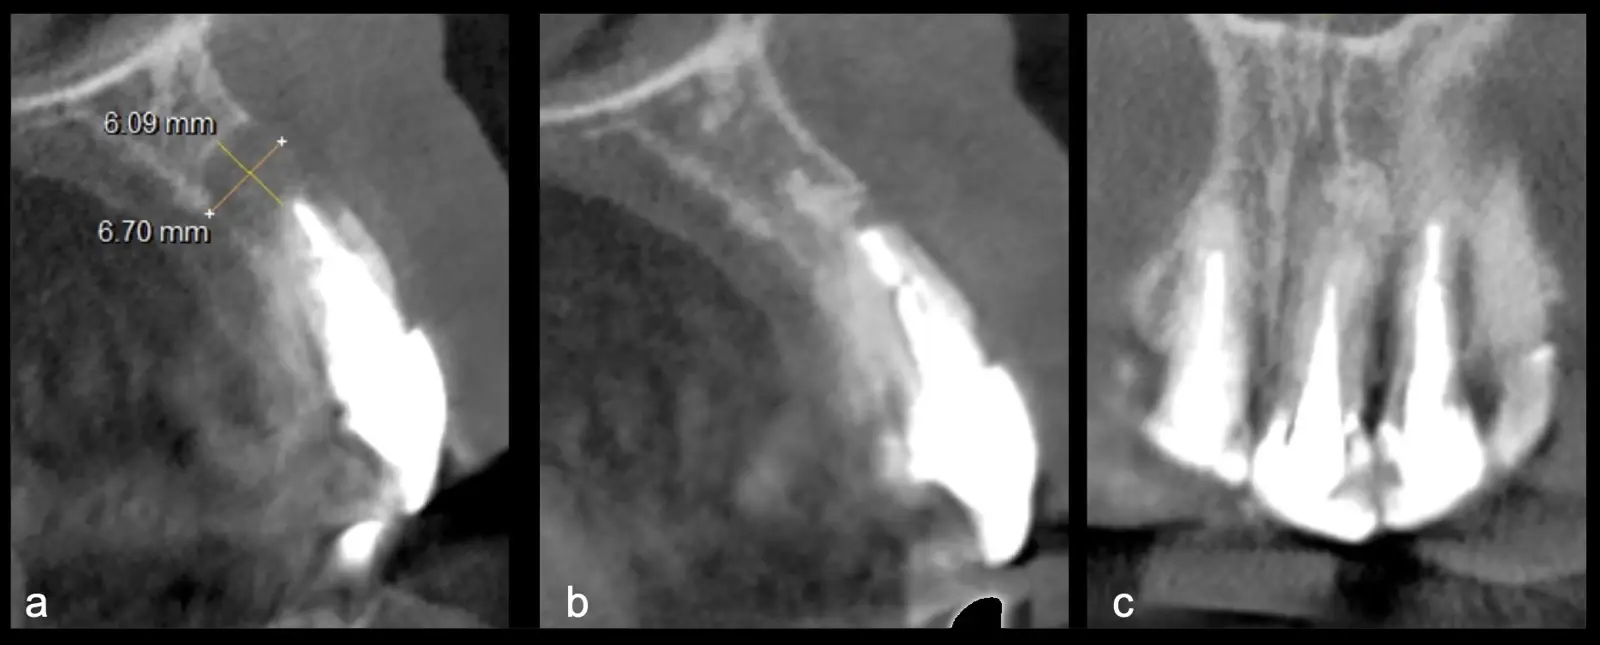

La microcirugía endodóntica apical busca conservar la mayor cantidad de longitud de raíz y de hueso circundante sano para no afectar la estabilidad de la pieza.11 Por ello, es ideal el uso de microscopios, elementos de magnificación, instrumental específico (insertos de ultrasonido endodónticos) y materiales de sellado eficientes para el tratamiento retrogrado. Su éxito es alto y evidencia una cicatrización ósea completa en el 74% de los casos al año de tratamiento.12 Cabe destacar que este logro está asociado también, a predictores propios de cada paciente, como la edad, tipo de pieza, profundidad de sondaje y extensión de la lesión.1 El uso complementario de la tomografía computarizada es resaltante como el instrumento imagenológico de elección para la etapa de planificación microquirúrgica,13 ya sea para una ejecución a mano alzada o con guías prefabricadas.14,15

Una vez limpia la zona apical, se corrobora la integridad de la raíz y se evalúa el grado de extensión de la lesión. Si el defecto óseo es pequeño, se procede a realizar la preparación del conducto y obturación retrógrada de ser el caso. Si el defecto óseo es de gran tamaño e inaccesible a los insertos, se procede a realizar un corte de por lo menos 3 mm de ápice radicular conteniendo los posibles conductos aún infectados11 empleando habitualmente insertos de borde aserrado con/sin marcas de medición para un trabajo seguro7 (Figura 7).

Aunque algunos autores recomiendan evitar los ángulos en bisel para no exponer excesivamente túbulos dentinarios por riesgo de una posterior microfiltración18, en la cirugía apical piezoeléctrica recomendamos realizar un bisel externo para tener un mejor acceso al ápice. La configuración de los insertos de piezoeléctrico permiten realizar un corte lo más cercano a los 0°-10° de bisel11 con acceso adecuado a la zona de posterior obturación (Figura 8).